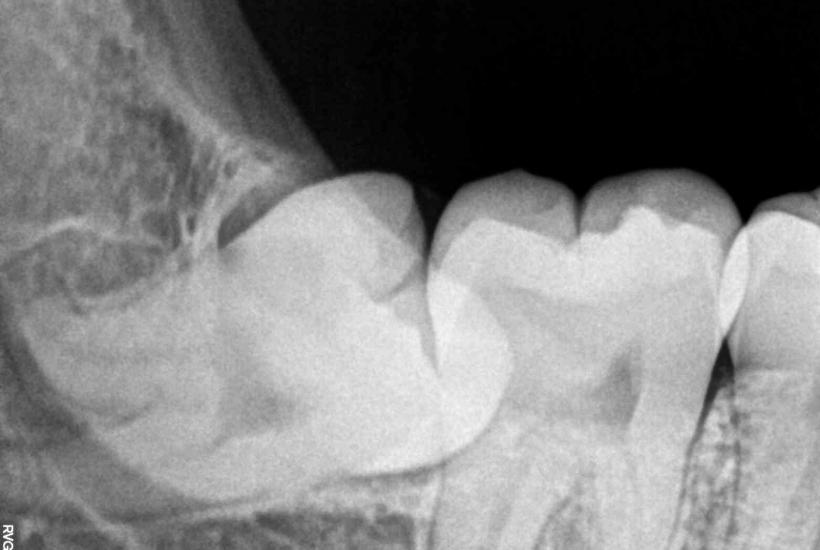

Статистика неутешительна: у 80 % взрослых зубы мудрости вызывают сложности. Их частичное прорезывание может стать причиной воспаления, боли и даже инфекций. Даже если они не доставляют серьёзных проблем, сам процесс их появления редко проходит безболезненно.

В Великобритании около 80 % этих зубов удаляют, а в США и вовсе чаще. Но не всё так однозначно: специалисты считают, что профилактическое удаление может быть ненужным. По данным исследований, лишь 12 % ретинированных (не полностью прорезавшихся) зубов действительно вызывают осложнения.